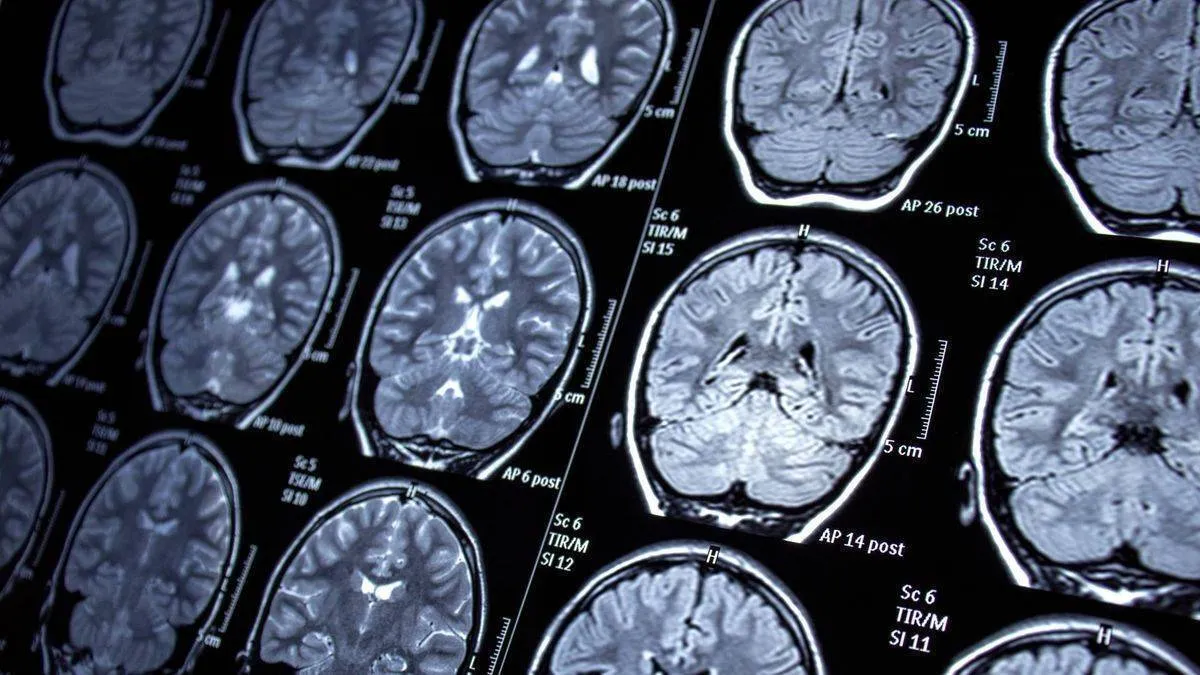

وی در این باره گفت : با کمک دستیار رباتیک، تصویربرداری ارتقا و ریسک انجام عمل جراحی به میزان قابل توجهی کاهش مییابد.